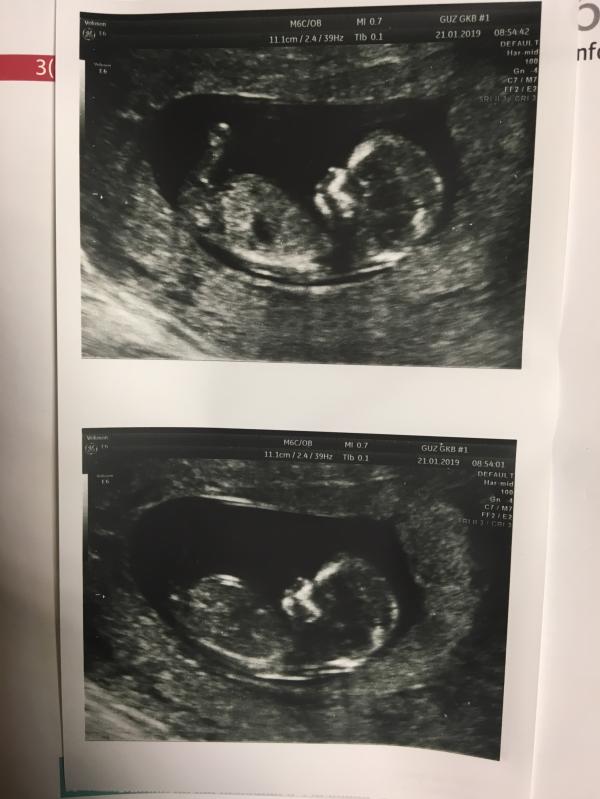

Первый скрининг ❤️ все чудесно! Такой хороший малыш, шевелился там 😭❤️ дергал ножками ❤️ чсс 155 уд/мин, ктр 52 мм, твп 1,4 мм. Предположили мальчика 😍 Но все равно, на сурова скрининг делают скомкано, все быстро быстро, конвеер, так что через пару недель схожу платно, разгляжу все как следует 😍 расти моя бусинка 😭❤️😍